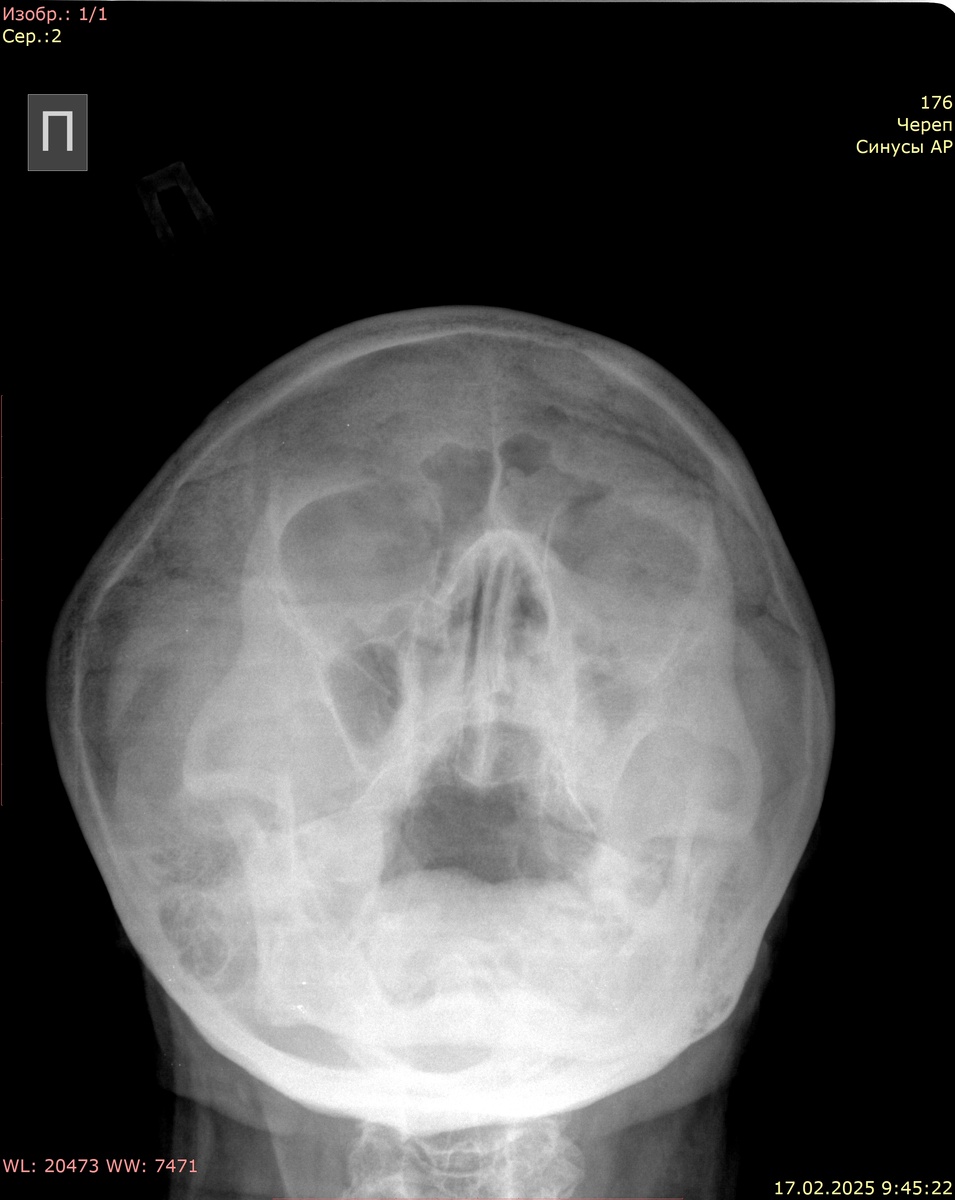

Визуализируются придаточные пазухи носа: верхнечелюстные, лобная, ячейки решетчатого лабиринта, клиновидная. Контуры пазух четкие, ровные. В левой лобной пазухе четкие извитые контуры патологической ткани. В обеих в/ч пазухах (больше слева) пристеночные утолщения. Уровней жидкости не определяется. Носовая перегородка по средней линии.

Заключение: картина двустороннего в/ч синусита. Susp. образование левой лобной пазухи (рекомендуется КТ пазух носа для уточнения)